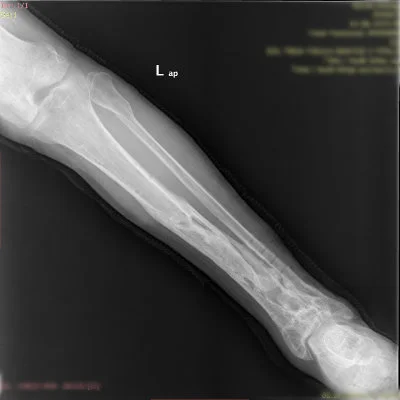

Görüntüleri büyütmek için resmin üstüne tıklayınız.